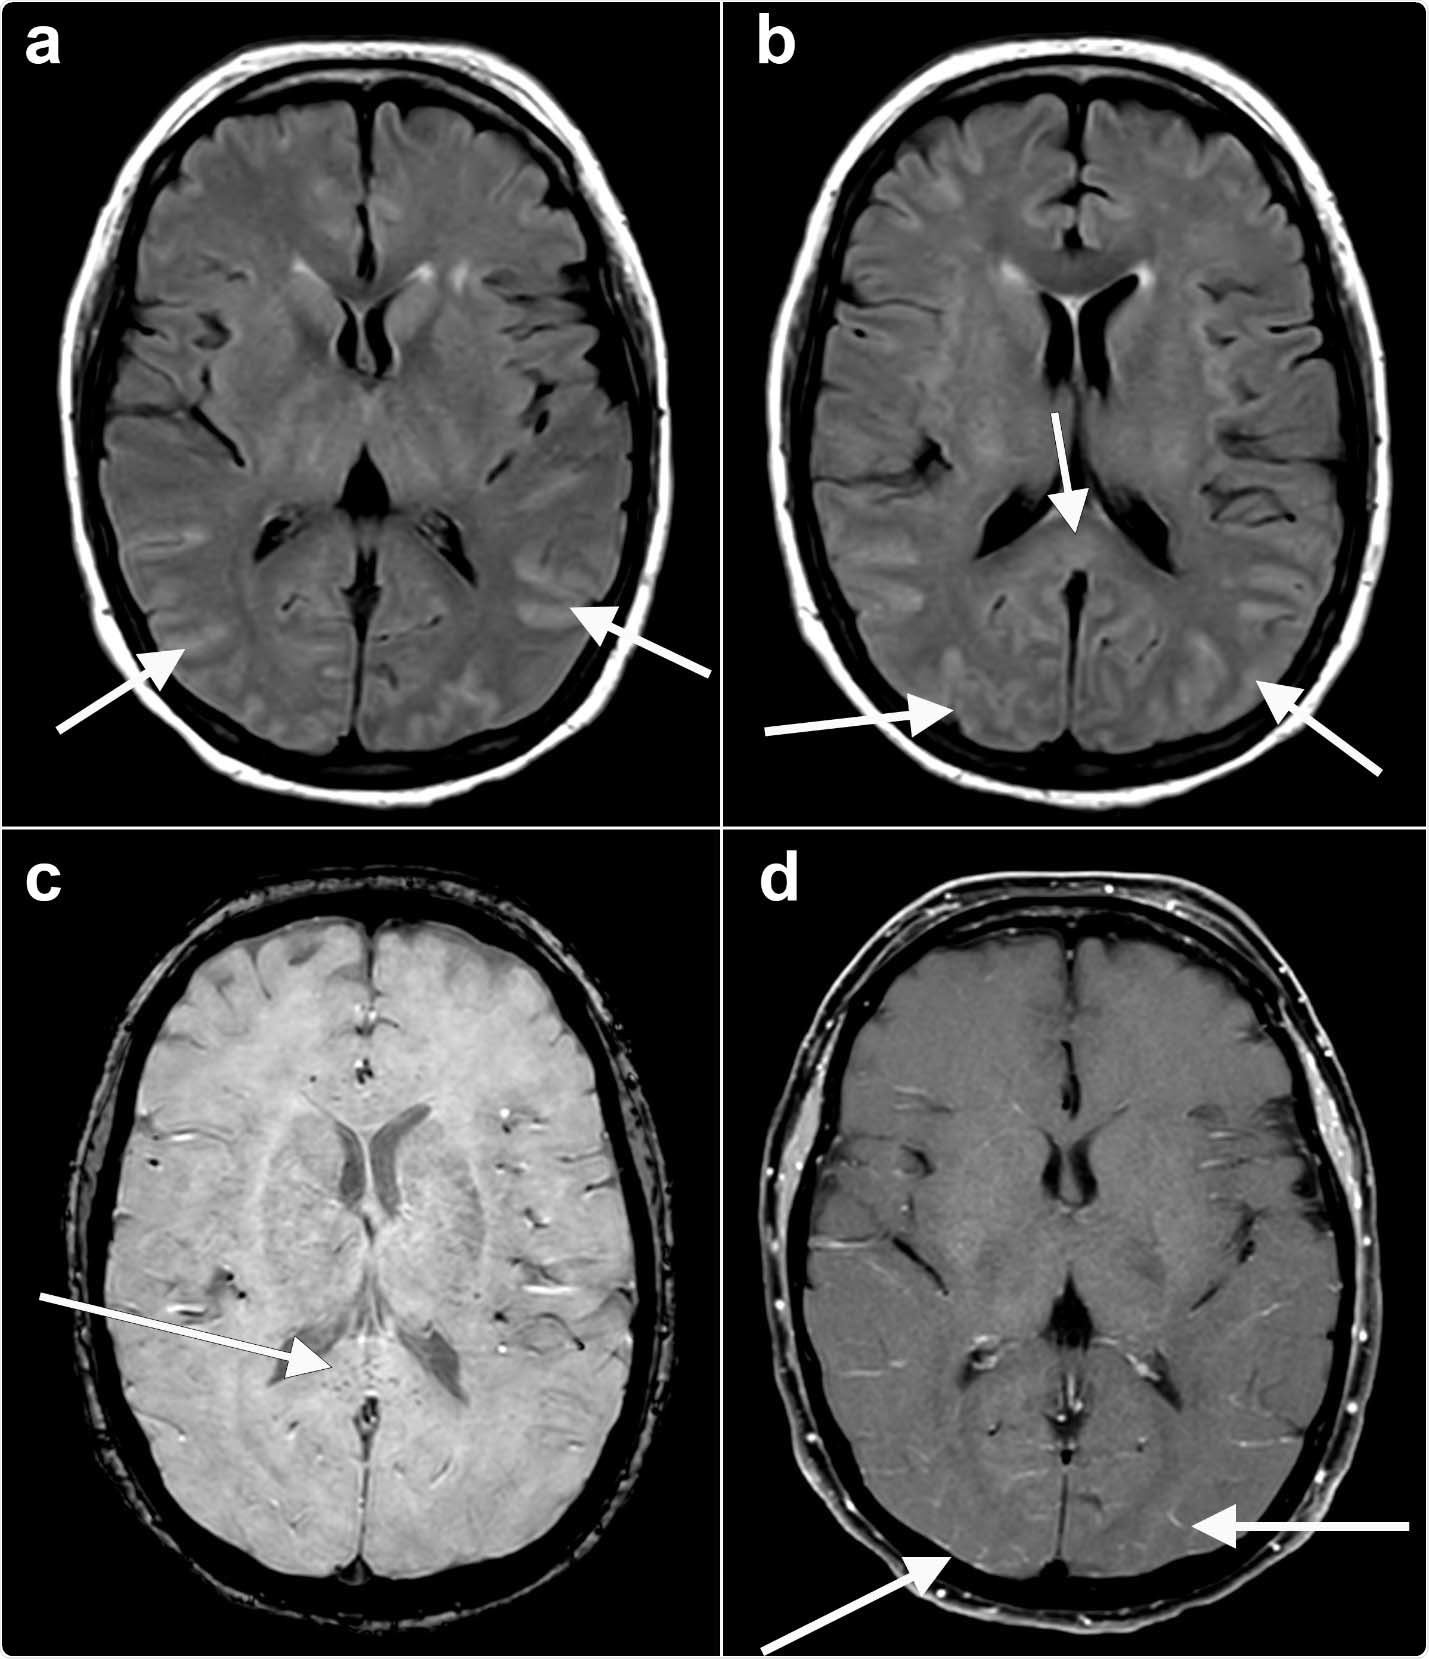

Axial fluid-attenuated inversion recovery (FLAIR) (a, b) images at the level of the basal ganglia show abnormal FLAIR hyperintense signal (arrows) affecting the bilateral occipital, temporal lobes. This appears almost sulcal suggesting a higher protein component within the cerebrospinal fluid. Note the elevated FLAIR signal in the splenium of the corpus callosum (arrow) suggesting parenchymal insult. Axial susceptibility weighted imaging (SWI) (c) at the level of the splenium of the corpus callosum shows small areas of susceptibility (arrow) in the splenium, likely related to microhemorrhage. Axial T1 (d) postcontrast with fat suppression at the level of the basal ganglia shows subtle, though true, enhancement (arrows) in the posterior sulci, arachnoid pial (leptomeningeal) pattern suggesting a degree of encephalitis.